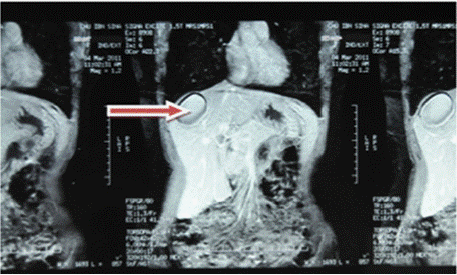

Ultrasound of the right liver (anterior sector) revealed a heterogeneous cystic image with a thin wall, suggestive of a type IV hydatid cyst. Abdominal CT confirmed a multiloculated cystic lesion containing fatty, calcified, and fluid components, suggestive of a hepatic teratoma. An MRI scan further supported the diagnosis, showing a grossly oval lesion in the hepatic dome measuring 57 × 48 mm. The lesion contained a fluid level with a supernatant displaying T1 hypersignal, T2 hyposignal, and a dependent portion in T1 and T2 isosignal, without enhancement after gadolinium injection — findings suggestive of a modified hydatid cyst.

Figure 2: Abdominal MRI C-, frontal section showing a rounded formation

with clear boundaries in the right liver with heterogeneous content.

Figure 3: Red arrow: C+ abdominal MRI frontal section showing a rounded

lesion in the right liver with a watery appearance and no contrast uptake at

the periphery.